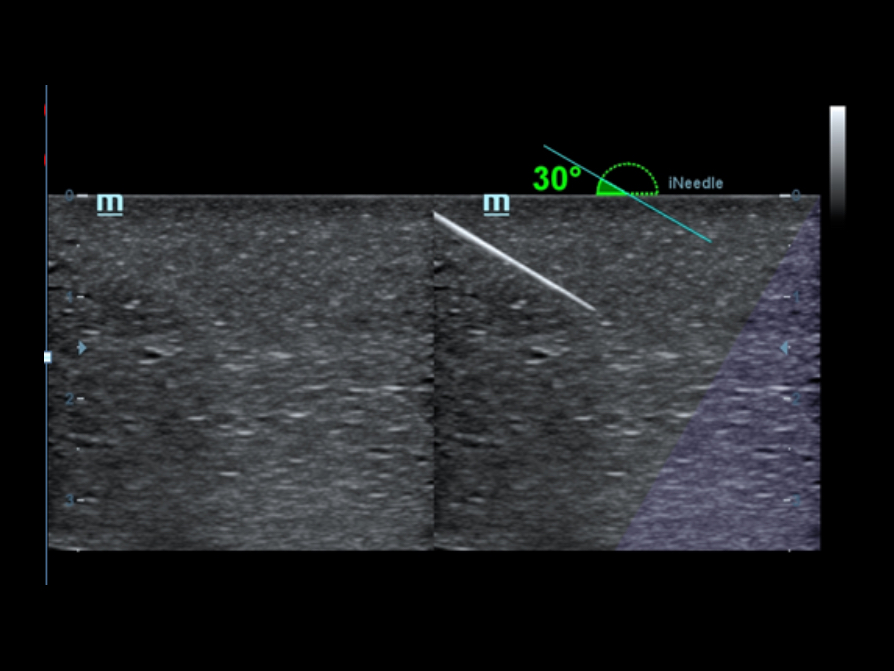

iNeedle?

Su herramienta para realizar una biopsia más profunda: permite ajustar la línea de exploración para obtener una mejor visibilidad de la aguja, los nervios y los vasos peque?os.